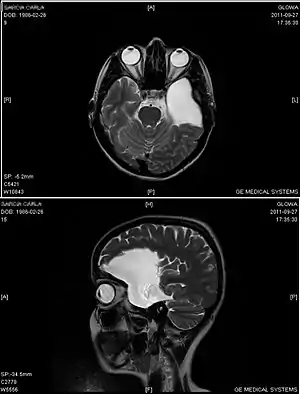

| Arachnoid cyst | |

|---|---|

![]() | |

| An MRI of a 25-year-old woman with left frontotemporal arachnoid cyst. | |